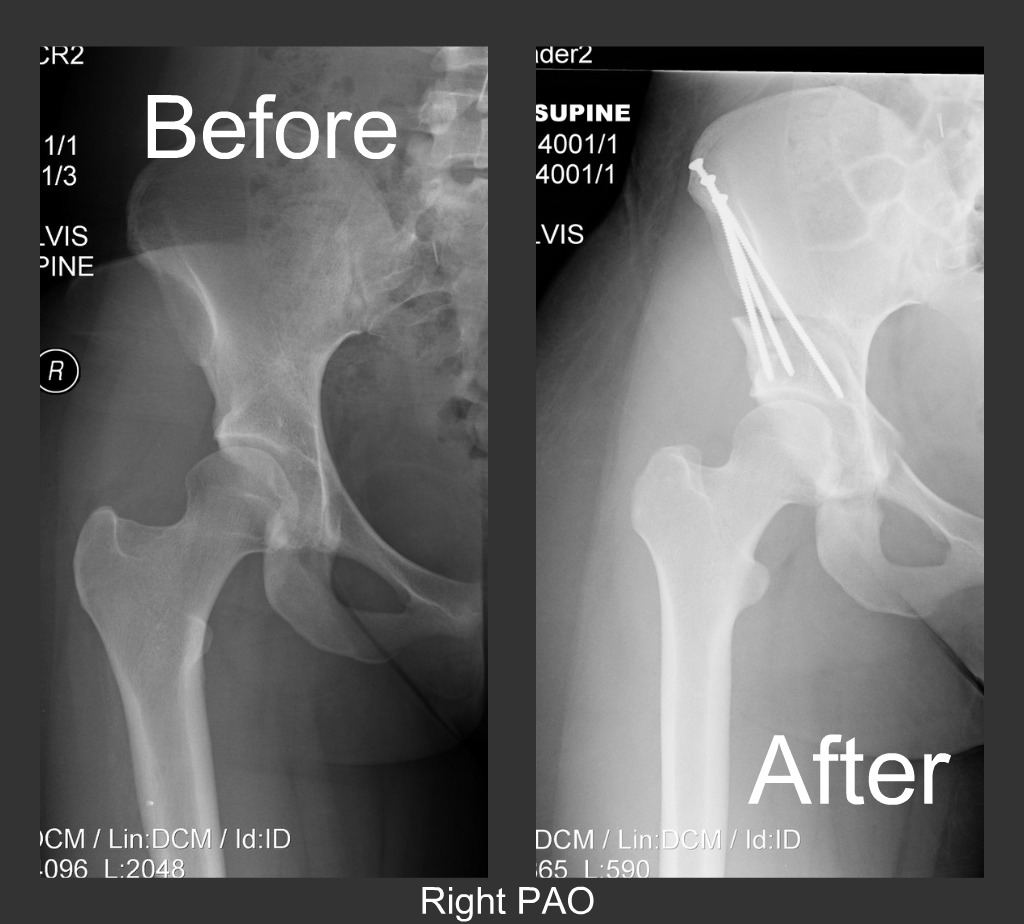

Danlos ehlers hypermobile childbearing hypermobility participants. Pao osteotomy ray periacetabular danlos ehlers rpao picnik collagefinal ortopediaweb

Periacetabular osteotomy (pao) ~ living with ehlers danlos syndrome. Hypermobility hypermobile disorders ehlers